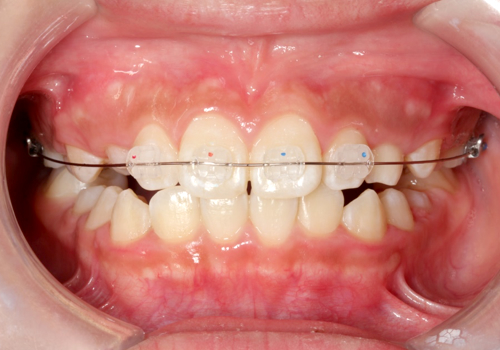

症例01. Sectional

混合歯列期や限局矯正に、ブラケットとワイヤーを用いて

並べます。凸凹だけでなく、噛み合わせの深さなども変え

られます。

| 治療内容 | 1:すきっ歯と八重歯が気になる 2:まず前歯を閉じる 3:スペースを使ってきれいに並べる |

|---|---|

| 期間 | 半年~1年 |

| 費用 | 300,000円+税 |

| リスク | 歯の動きに伴ったむずがゆさや軽度の痛みが出る可能性があります。 数日程度で慣れてしまいます。 |